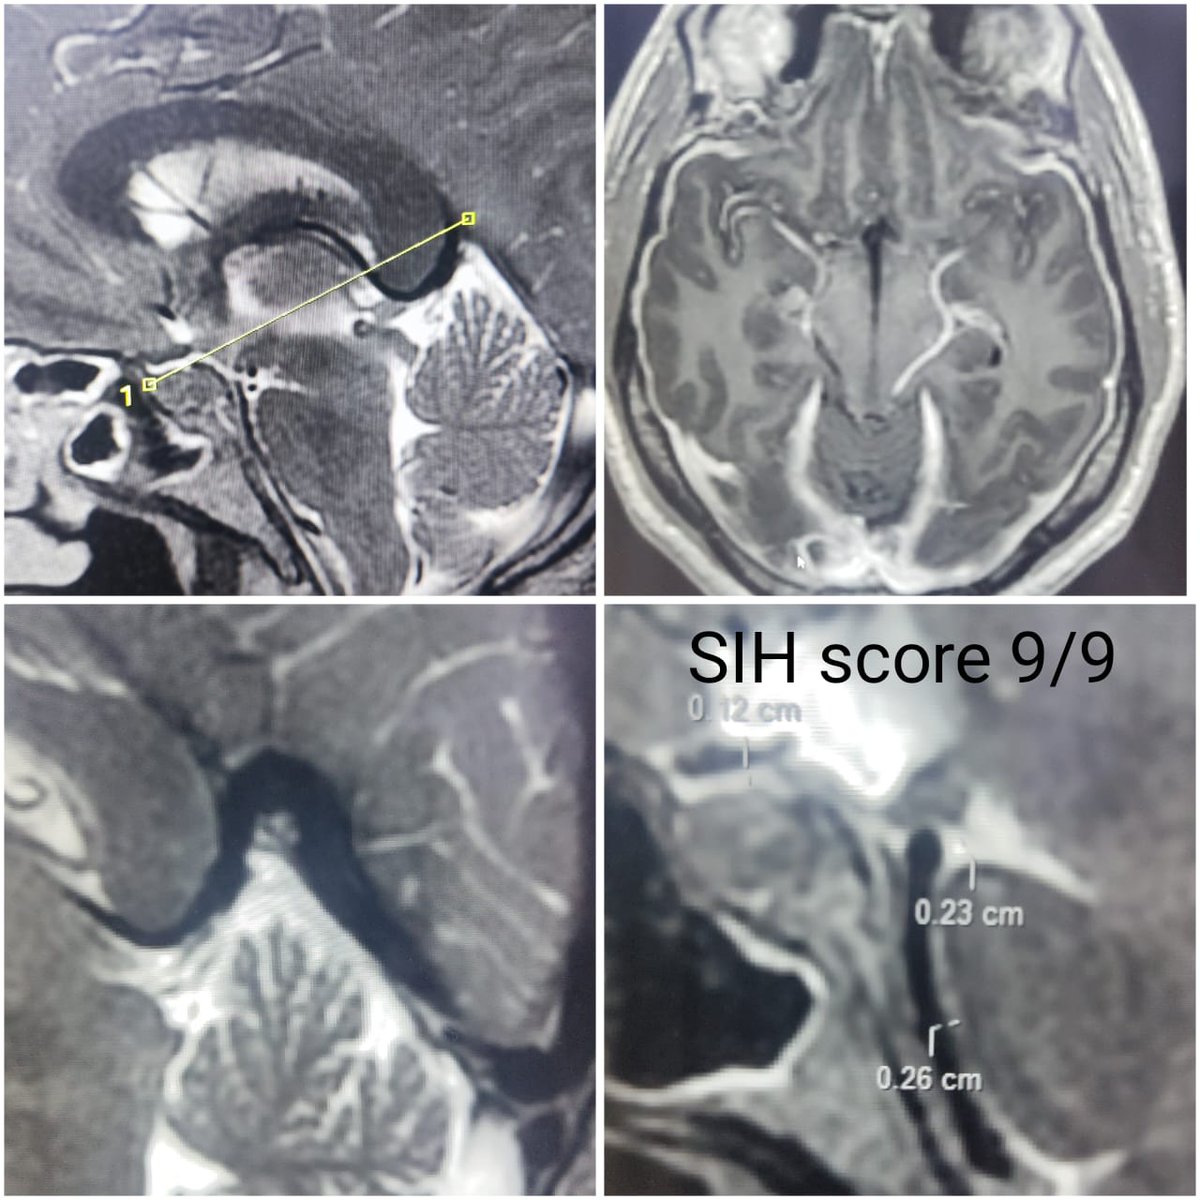

Symptomatic Type 1A spinal CSF leak due to bony spur. SIH score 9/9, treated with EBP and hopefully it will offer some long term benefits! #sih #SpinalCSFleak #headache #EBP @spinalCSFleak @The_ASSR @SpinalCSFCanada @CarolinaIten

SharathKumarGG7's tweet image. Symptomatic Type 1A spinal CSF leak due to bony spur. SIH score 9/9, treated with EBP and hopefully it will offer some long term benefits! #sih #SpinalCSFleak #headache #EBP @spinalCSFleak @The_ASSR @SpinalCSFCanada @CarolinaIten